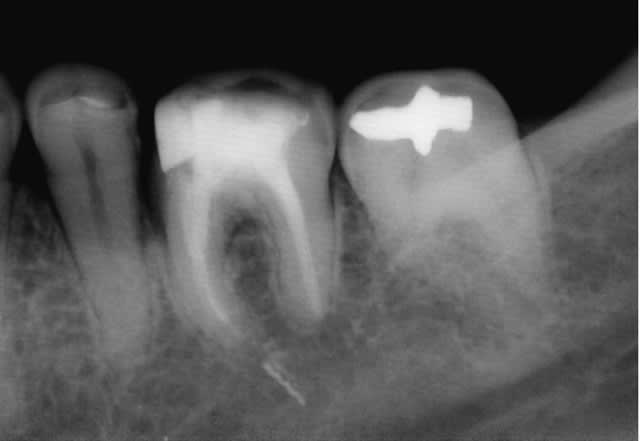

Monté sur son giromatic, le rispi neuf est d'abord passé dans le canal disto-vestibulaire ; juste après, je me laisse surprendre par un effet de vissage (sur giromatic ???) et me retrouve avec l'instrument fracturé bien au dela de l'apex.

2nde : je viens de casser le rispi